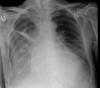

EAP

Edema cisural en EAP